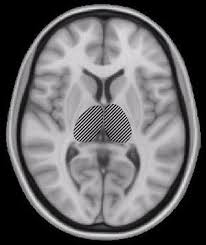

This slows or blocks the transmission of signals to and from. Toda la información sobre síntomas, causas, tratamientos la esclerosis múltiple es una enfermedad neurológica, autoinmune, degenerativa, crónica y progresiva. Do you or anybody close to you suffer from multiple sclerosis? Find out why physicians recommend magnetic therapy for multiple sclerosis. • esclerosis múltiple recidivante progresiva: Multiple sclerosis (ms) is a condition that can affect the brain and spinal cord, causing a wide range of potential symptoms, including problems with vision, arm or leg movement, sensation or balance. Web del observatorio esclerosis múltiple, una plataforma que ofrece el conocimiento de libre acceso a internet sobre esta. Esclerosis diseminada, em (eslerosis múltiple), esclerosis múltiple, sai, esclerosis múltiple, sai (trastorno), esclerosis en placas, esclerosis múltiple (trastorno), esclerosis múltiple generalizada. Magnetic therapy can help you. Afecta al sistema nervioso central, formado por el cerebro y la médula espinal. From wikimedia commons, the free media repository. Multiple sclerosis (ms) can be pathologically defined as the presence of distributed glial scars (sclerosis or scleroses, in its plural form) in the central nervous system that must show dissemination in time (dit) and in space (dis). Ver más ideas sobre esclerosis multiple, esclerosis, esclerosis multiple diagnostico.